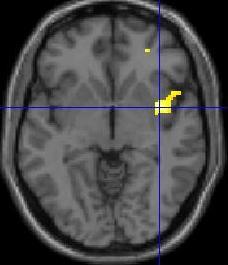

Hirnaktivierung unter Schmerzreizung Universitätsklinikum Essen